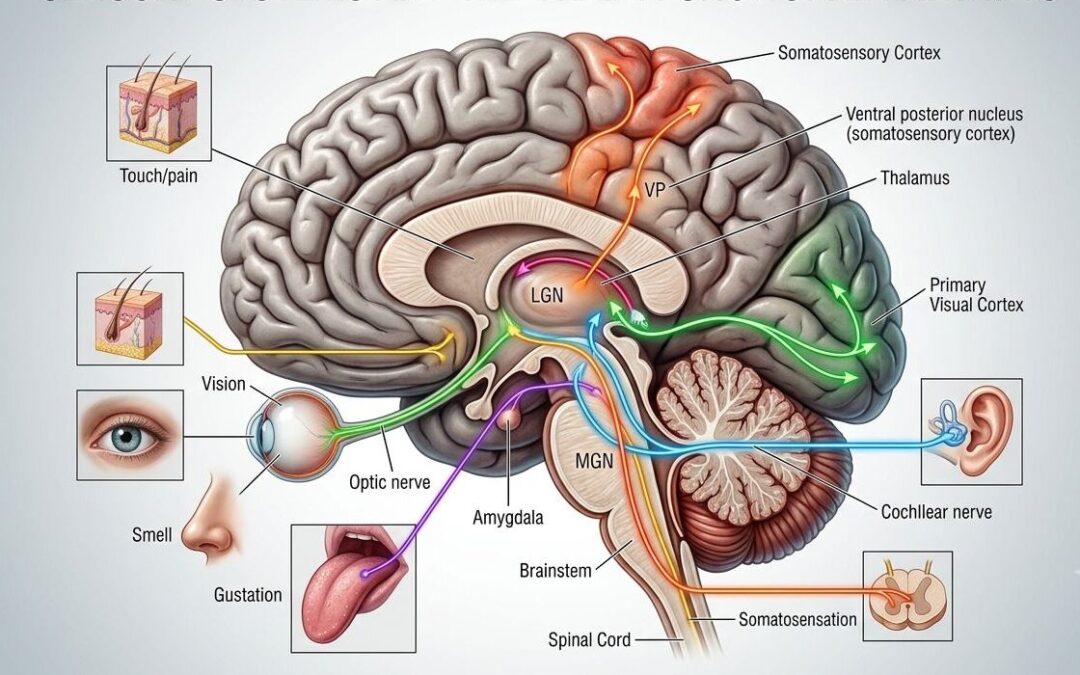

Obesity is no longer viewed as a simple imbalance between caloric intake and expenditure. It is a chronic metabolic condition influenced by endocrine signaling, inflammatory pathways, insulin resistance, and gut-host interactions. Within this framework, the microbiome functions less as a secondary contributor and more as a dynamic metabolic organ. Its composition affects energy harvest efficiency, short-chain fatty acid production, bile acid metabolism, systemic inflammation, and satiety regulation.

The rapid adoption of GLP-1–based therapies has reshaped patient expectations. These agents have demonstrated meaningful effects on appetite regulation, gastric emptying, and glycemic control. Emerging data suggest that GLP-1 therapies may also influence gut microbial composition, and that baseline microbial diversity may, in turn, affect therapeutic response. If confirmed in larger prospective studies, this bidirectional interaction could support more personalized metabolic protocols.

Modern obesity care must move beyond focusing solely on kilograms lost. Metabolic quality matters. Insulin sensitivity, inflammatory burden, hepatic function, body composition, and hormonal balance are central to long-term cardiometabolic health. The microbiome intersects with each of these domains. Short-chain fatty acids produced by gut bacteria participate in immune regulation and insulin signaling, while dysbiosis has been associated with adipose tissue inflammation and non-alcoholic fatty liver disease.